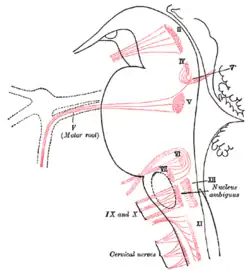

The cranial nerve nuclei schematically represented; dorsal view. Motor nuclei in red; sensory in blue. Nuclei of origin of cranial motor nerves schematically represented; lateral view.

Nuclei of origin of cranial motor nerves schematically represented; lateral view. Cross section of the lower pons showing the facial motor nucleus and part of the root of the facial nerve.